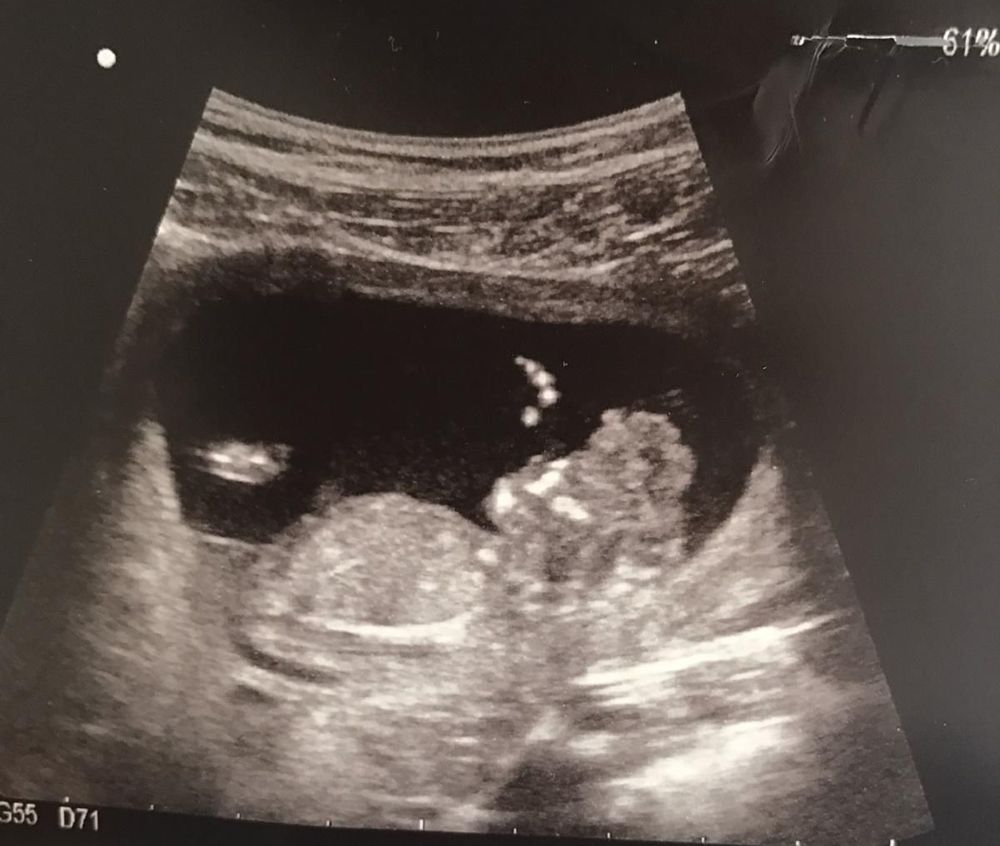

Smith was excited for her following scans. This time, though, it revealed that one of the babies had acrania and would be unlikely to survive outside of the womb.

“The baby with acrania wouldn't have made it, but the complication was that they were twins," she said.